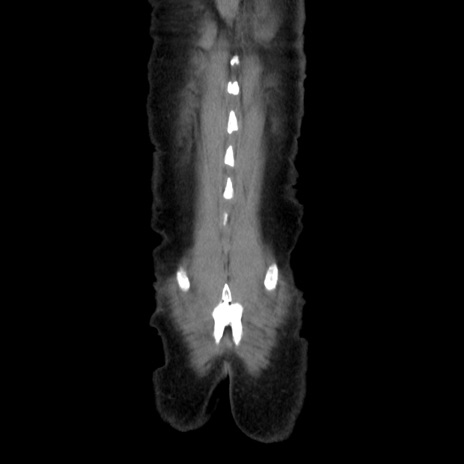

横断像